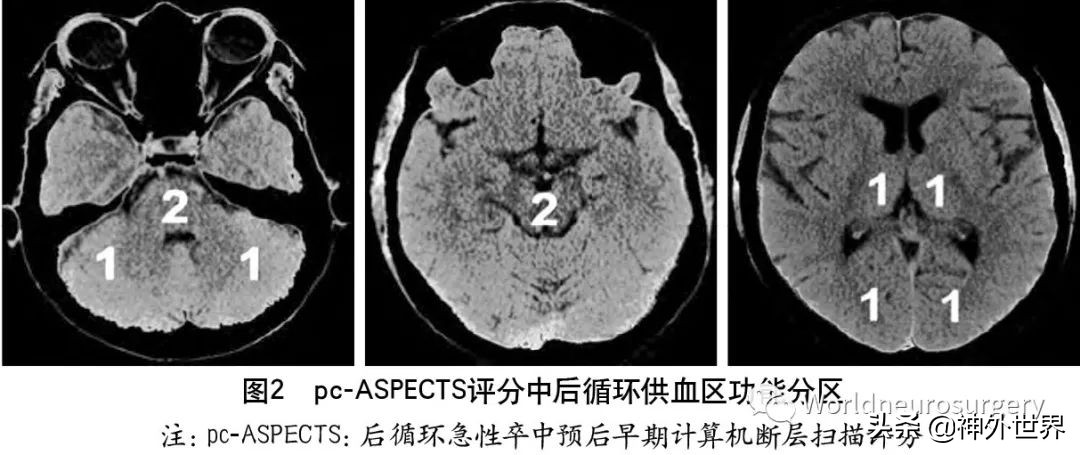

为评估后循环梗死患者早期梗死情况,PUETZ等 建立了评估后循环的AIS预后早期CT评分(posterior circulation Acute Stroke Prognosis Early CT score,pcASPECTS)。pc-ASPECTS总分也是10分:双侧丘脑和小脑各1分,双侧大脑后动脉供血区各1分,中脑和脑桥为2分(图2)。